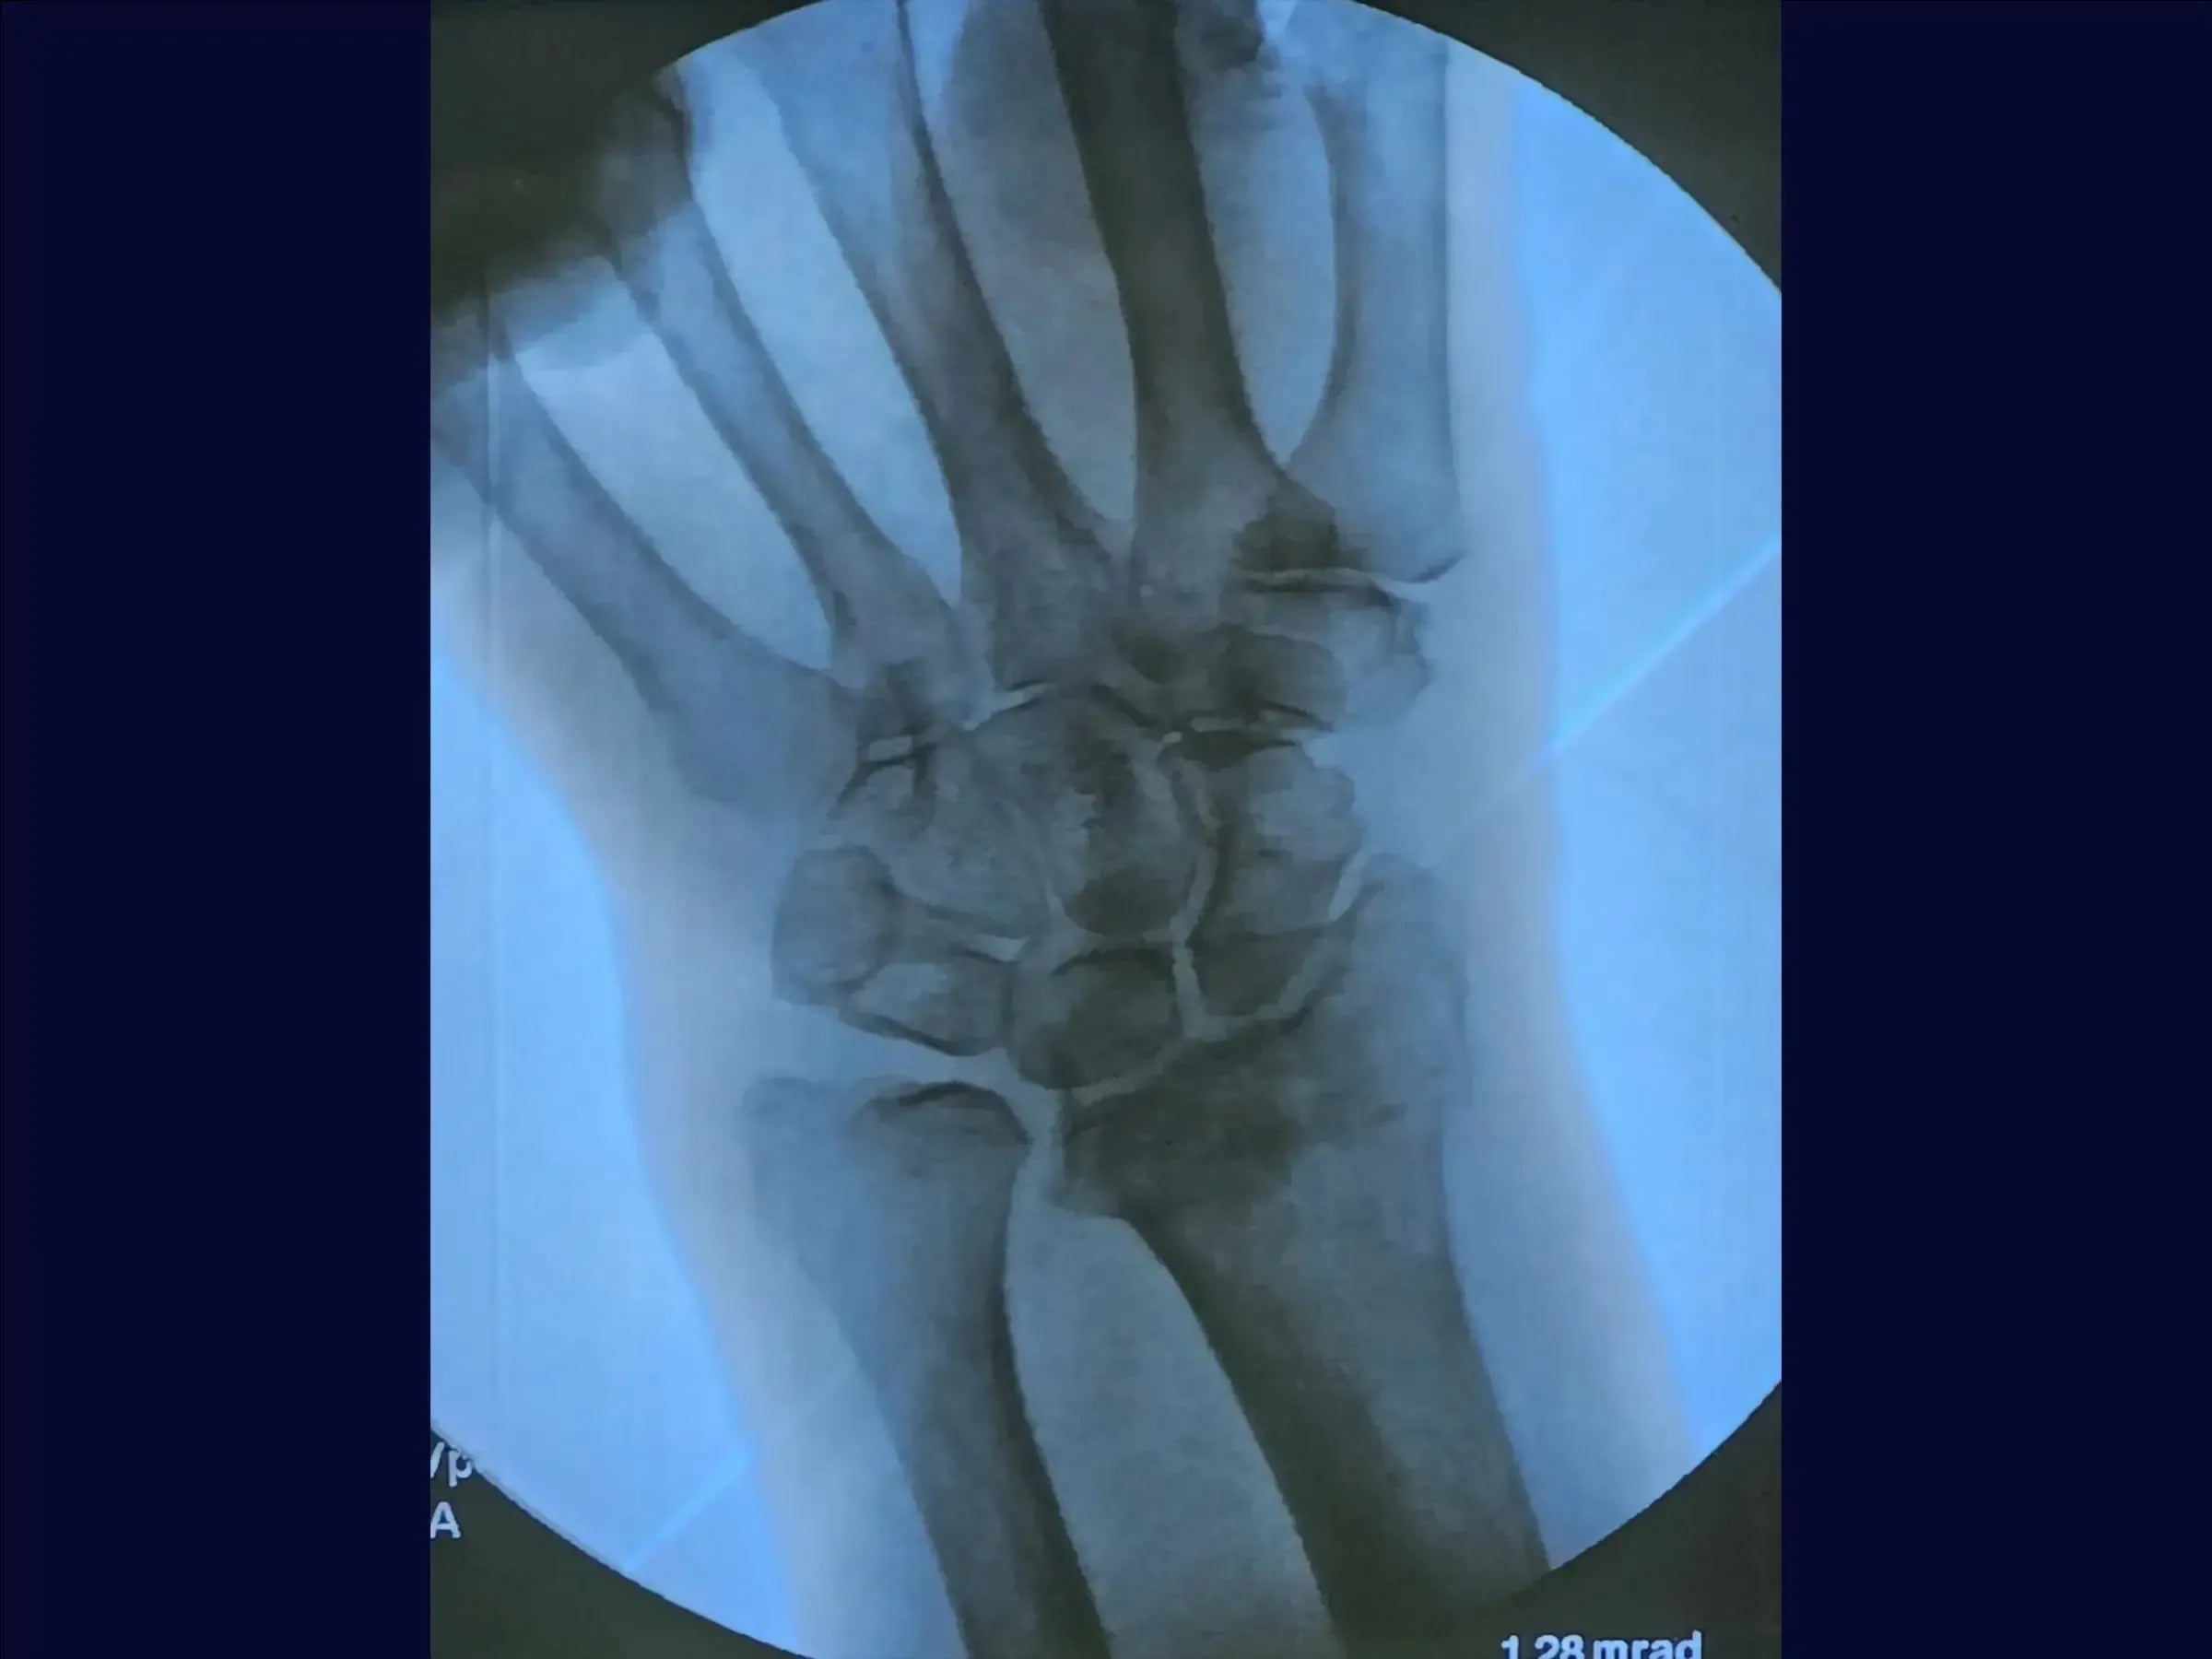

- Avaliação e Acesso Cirúrgico: O treinamento inicia com a avaliação radiográfica para planejamento da redução e implante. Aborda a demarcação do acesso sobre o tubérculo de Lister, identificação dos compartimentos musculares e rebatimento de tendões para expor a fratura.